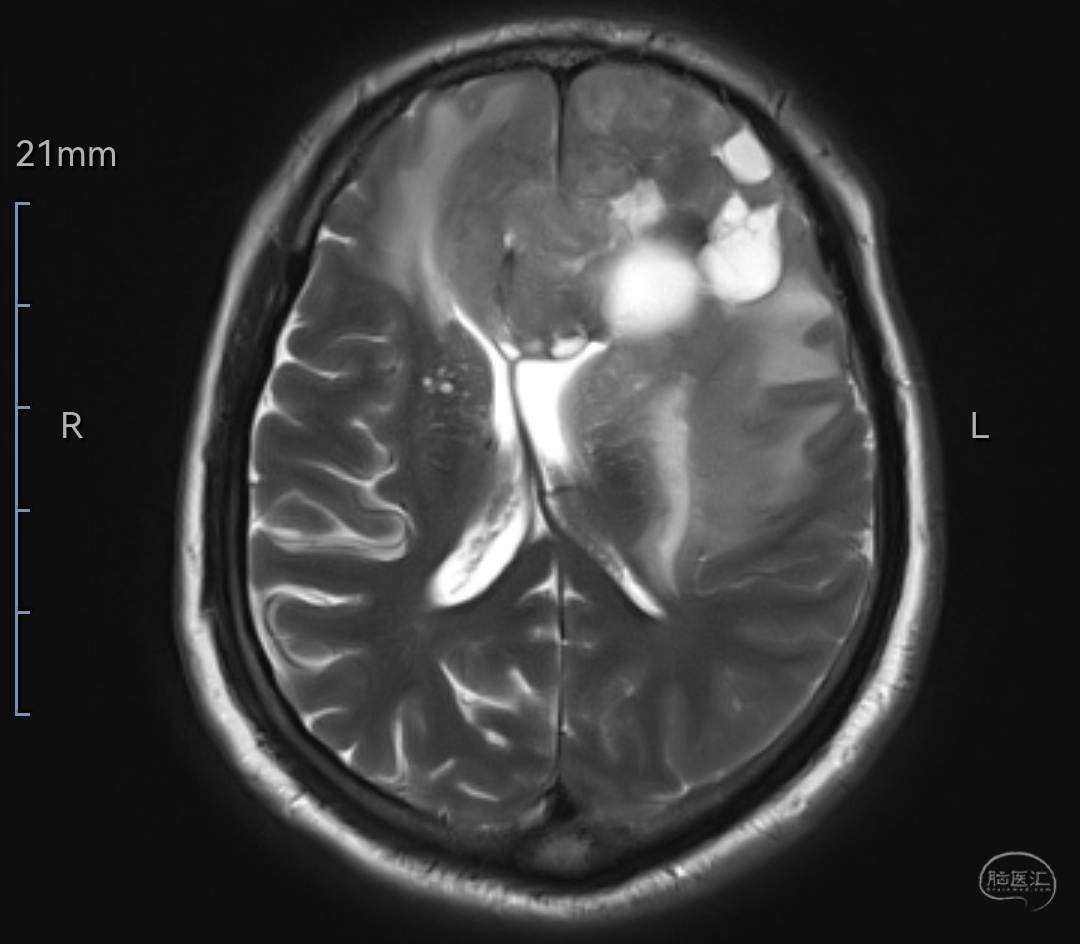

MRIT2相轴位示肿瘤等高信号,位于双侧额叶,左侧为主,已侵犯至胼胝体嘴、膝部及左侧颞岛叶,伴有明显水肿